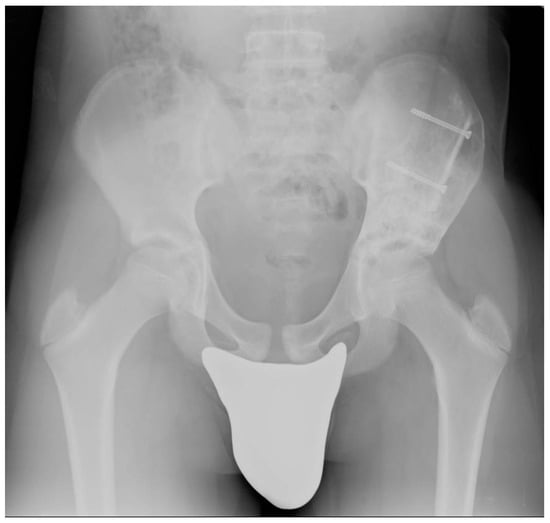

2. Materials and Methods

3. Results